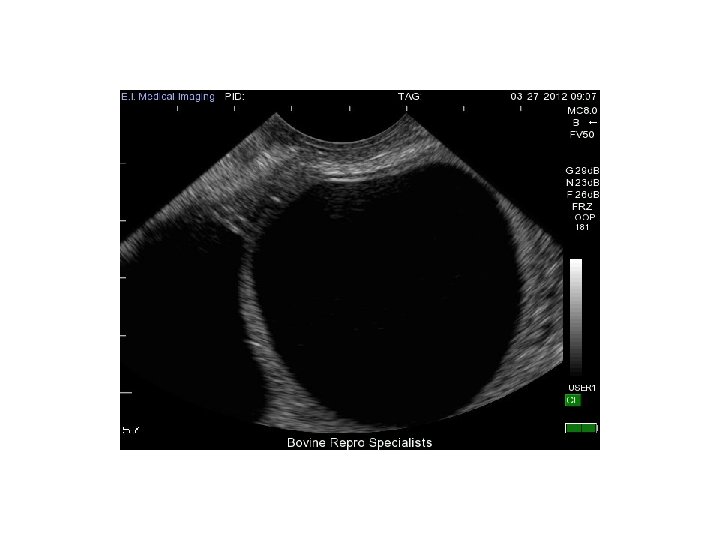

FOLLIKELCYSTA

ANAMNES: • 19 -årig 0 G kommer på remiss från kirurgakuten, ”gynekologisk orsak till buksmärtor? ”. En dags anamnes på högersidiga buksmärtor, initialt runt navelplan, nu ffa höger fossa. Konstant smärta. Illamående och kräkning. Feber.

STATUS: • Buk: Palpöm höger fossa, direkt och indirekt släppöm. • VVP: Rodnad slemhinnor. Vit, flockig fluor utan dålig doft. Portio insp ua. Ruckömhet. Uterus palperas oöm, mobil, anteflekterad. Vän adnex palperas en mjuk utfyllnad, oöm. • Lab: CRP 35, LPK 17.

ULTRALJUDSBILD: 4 cm

MAKROSKOPISK BILD:

DISKUSSION FOLLIKELCYSTA: • Hur uppstår en follikelcysta? • Någon åtgärd ur gynekologisk synvinkel? – Om ja, vad? – Om nej, ska pat följas upp? • Handläggning om pat vore en postmenopausal kvinna?